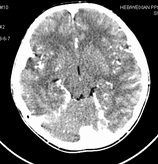

男,10岁,因近来常头痛就诊。先平扫拟诊右侧脉络膜裂囊肿,后薄层(3mm)扫描见此灶与右侧脑室后角相通,且向内几乎与鞍上池相连,并见一血管影沿其走形 (可能是脉络膜前动脉)。1。请教:脉络膜裂或脉络膜裂囊肿与侧脑室颞角或鞍上池相通吗?好像谁说脉络膜裂是脉络膜从外侧裂向侧脑室移行的裂隙。请高手讲讲这点的解剖关系。2。建议:对于老年患者,有丘脑附近特别是右丘脑附近的近似腔隙性梗死灶,临床症状不明显的,应做3mm薄层扫描,看病灶向下是否与侧脑室颞角相连,以免误诊。

薄层强化:

应该是侧脑室下脚.

侧脑室下角

考虑侧脑室下角。

侧脑室下角;扫描位置不标准。